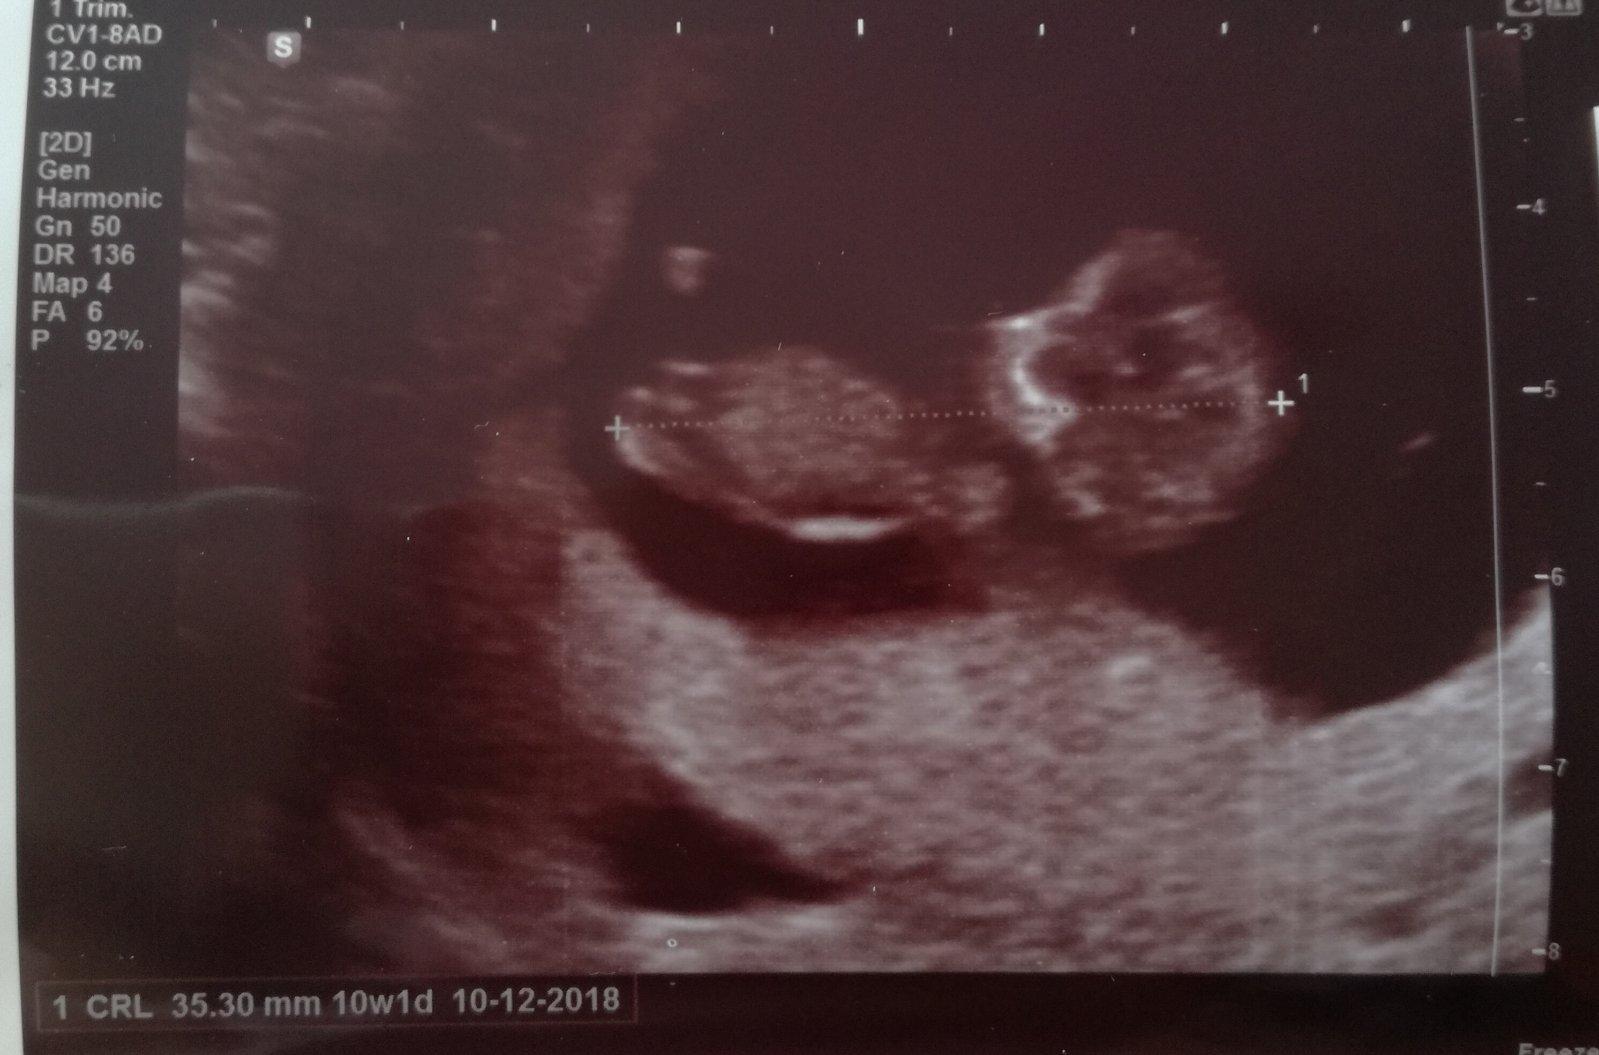

@sarinkaropuska tak dnešní kontrola 8+1 vše zatím v pořádku a měříme necelá 2cm.a je pěkně akční vrtěl tam sebou že doktorka jo tam naháněla.jinak kontrola 15.5 na krev a už mám dostat i prukazku

@radkey ahoj dnes kontrola 7+1

A čekáme dvojcatka ❤❤🍀🍀

@radkey ahoj beru utrgestan od zacatku trasferu a beru ještě estrofen.dnes kontrola jeden plod odpovídá 7+4a druhý 8+0 ❤❤zitra zavolam do Pronatalu spatne my napsali posledni ms místo 21.3 napsaly 18.3-(